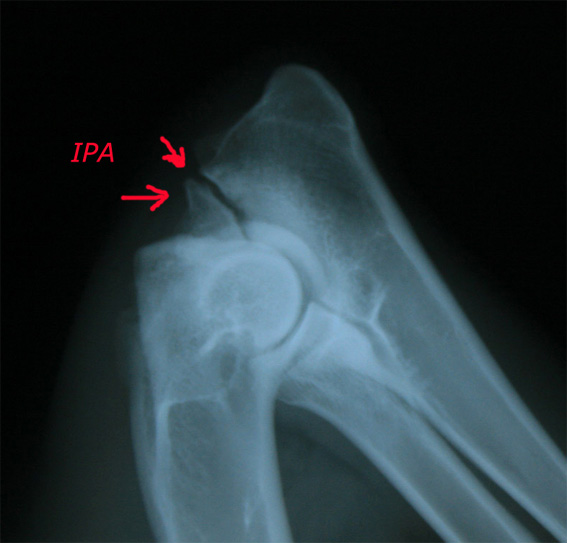

für den im Folgenden besprochenen IPA. 3. IPA (Isolierter Processus anconaeus) Beim Processus anconaeus (PA) handelt es sich um einen Knochenvorsprung der Elle, dessen Wachstumsfuge im Alter von 16 bis 20 Wochen geschlossen sein sollte. Fehlt diese knöcherne Verbindung, liegt ein Krankheitsbild vor, das folgende Ursachen haben kann: Ein verzögertes Längenwachstum der Elle, dadurch Druckveränderung und Irritationen, führt in seiner Wachstumsfuge zu Störungen der Verknöcherung und zum Isolierten PA. Bei einer zu engen Gelenkpfanne (Incisura trochlearis) der Elle entsteht Druck auf den PA und dem medialen Kronfortsatz. IPA tritt häufig bei Deutschen Schäferhunden auf. Bis zum Alter von sieben Monaten kann versucht werden den PA mit einer Schraube zu fixieren. Danach ist eine Entnahme angezeigt.

Ellenbogens hervorgerufen werden können. Röntgenbild DSH, 12 Monate, linkes Ellbogengelenk, seitlicher Strahlengang, gebeugtes Gelenk. IPA. Nicht dislozierter isolierter Processus anconaeus . Eine Stufenbildung zwischen Radius und Ulna ist nicht erkennbar. Hintergrund: Das Ellbogengelenk, ein so genanntes Scharniergelenk, wird von drei Knochen gebildet. Der Oberarmknochen (Humerus) formt die Gelenkwalze. Die Gelenkpfanne wird zum größten Teil von der Gelenkfläche der Speiche gebildet, die etwa 80 Prozent der Last übernimmt. Von hinten wird die Gelenkwalze von einer halbmondförmigen Aussparung der Elle (Incisura trochlearis) umfasst. Das obere Ende dieses Gelenkabschnittes wir vom Processus anconaeus gebildet, der als zapfenförmiger Fortsatz in eine entsprechende Aussparung des Oberamknochens reicht. Am unteren Ende finden sich der kleinere äußere und der erheblich größere innere Kronfortsatz (Processus coronoideus lateralis und medialis), die den Kopf der Speiche von hinten umfassen. Berater: Dr. Bernd Tellhelm, Justus-Liebig-Universität Gießen, Fachbereich Veterinärmedizin, Chirurgische Veterinärklinik Quelle: http://www.dgk.de |